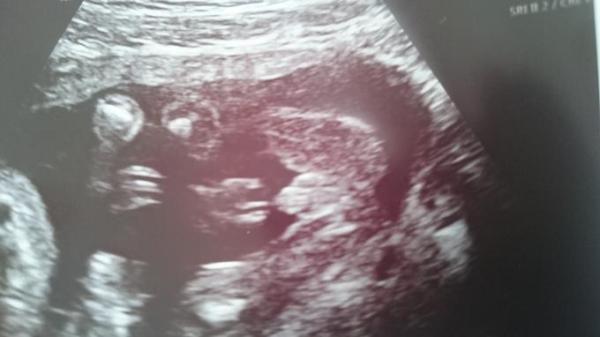

Hi Hatte vor kurzem ein jungen outing. vorab wir freuen uns natürlich riesig auf einen jungen!! Bin mir nur so unsicher weil das rechts und links nicht wie Hoden aussehen. Deshalb meine Frage könnt ihr es auch als junge erkennen, oder kann ich schon blau shoppen? Liebe grüße

Bild zu Könnt ihr es auch erkennen? - Schwanger - wer noch? Rund um die Schwangerschaft

Also ich erkenne es. Sieht genauso aus wie bei uns und der ist definitiv ein kleiner Kerl

Definitiv ein junge sah bei unseren beiden auch ganz genau so aus

Sieht aus wie bei meinen beiden Jungs. Bei Jungs ist es ja immer einfacher zu erkennen. Bei Mädchen eher schwierig und nicht so eindeutig.

Eindeutiger geht es nicht, ich habe 4 Jungs und habe da nen geschulten Blick. Ein kleiner Bubi auch für Dich